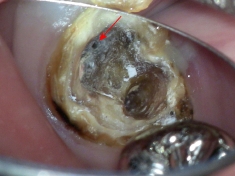

根の治療中に異物を発見。

マイクロスコープを使用することにより、異物がしっかり確認できるため除去可能です。